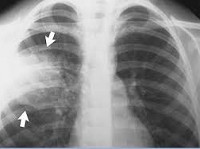

Рентгенологическое исследование (рентгенография легких в двух проекциях) позволяет визуализировать пневмоническую инфильтрацию легочной ткани (в виде интенсивного затемнения доли или очаговой тени), определить наличие плеврального выпота. С целью дифференциальной диагностики с раком легкого, туберкулезом, ателектазом применяется линейная и компьютерная томография (КТ легких).

Вместе с анализами крови врачи обычно берут образцы мокроты. Обязательное условие – проведение рентгенографии, которая поможет определить, насколько поражены болезнью легкие. Если врачи подозревают скопление экссудата, возможно, что будет назначено УЗИ, по результатам которого будет назначена дополнительная терапия.